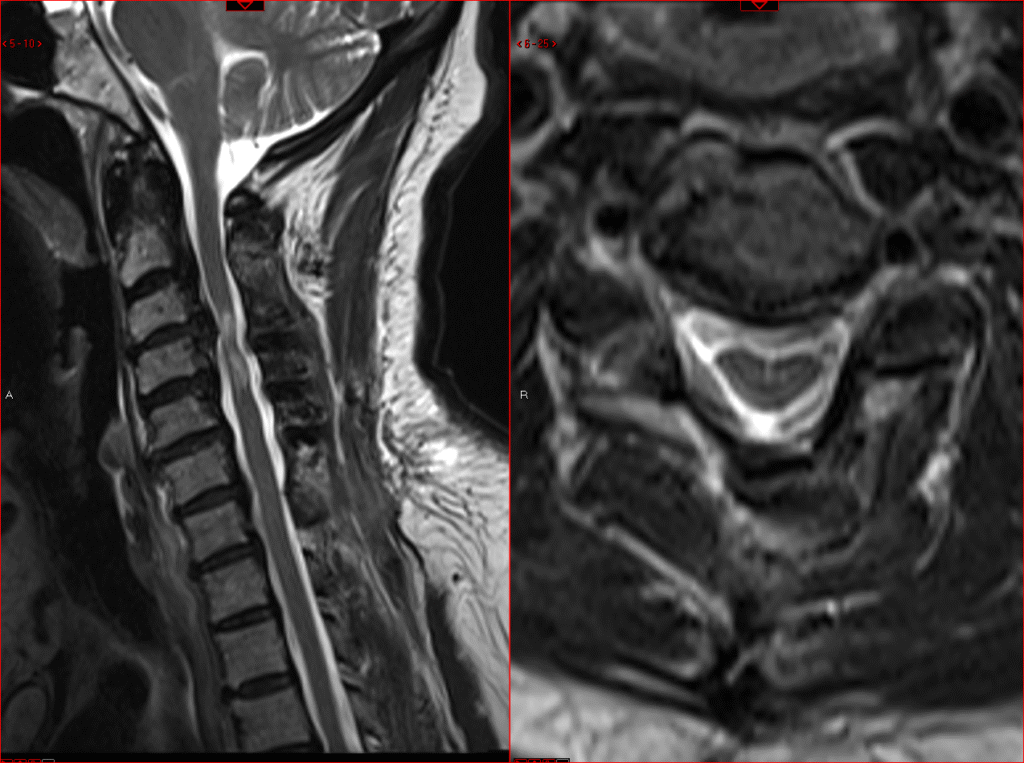

C1-2 fusion

Posterior Cervical Spine Surgeries

Posterior Cervical Fusion